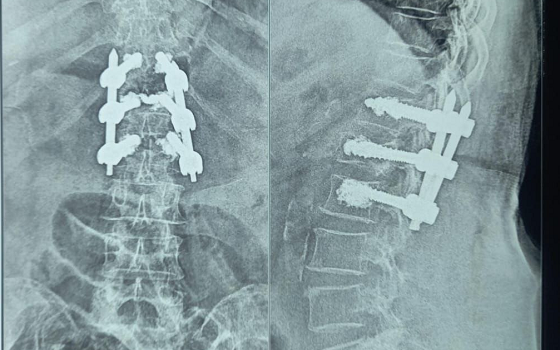

Dr. Somashekar D is an experienced spine surgeon in Bangalore. He is currently practising as a Consultant - Spine Surgery at Manipal Hospital Jayanagar, Bangalore. With nearly 10+ years of expertise in spine care, Dr. Somashekar has established himself as a highly skilled spine surgeon, contributing to over 1,500+ spine surgeries independently, ranging from simple decompressions to complex spinal reconstructions. His practice is deeply rooted in precision-based techniques and evidence-guided clinical protocols, ensuring both safety and long-term functional outcomes for his patients. He is a top spine surgeon in Jayanagar.

We offer comprehensive treatment for spine issues that is on par with any leading spine center worldwide. Our services encompass both non-surgical and surgical treatments tailored to address your specific condition. Our expertise covers a wide range of spine surgeries, including minimally invasive spine surgery, cervical spine surgery, scoliosis surgery, and complex spine surgeries.

• Spine trauma

Covers a wide range of spine surgeries, including complex spine surgeries.